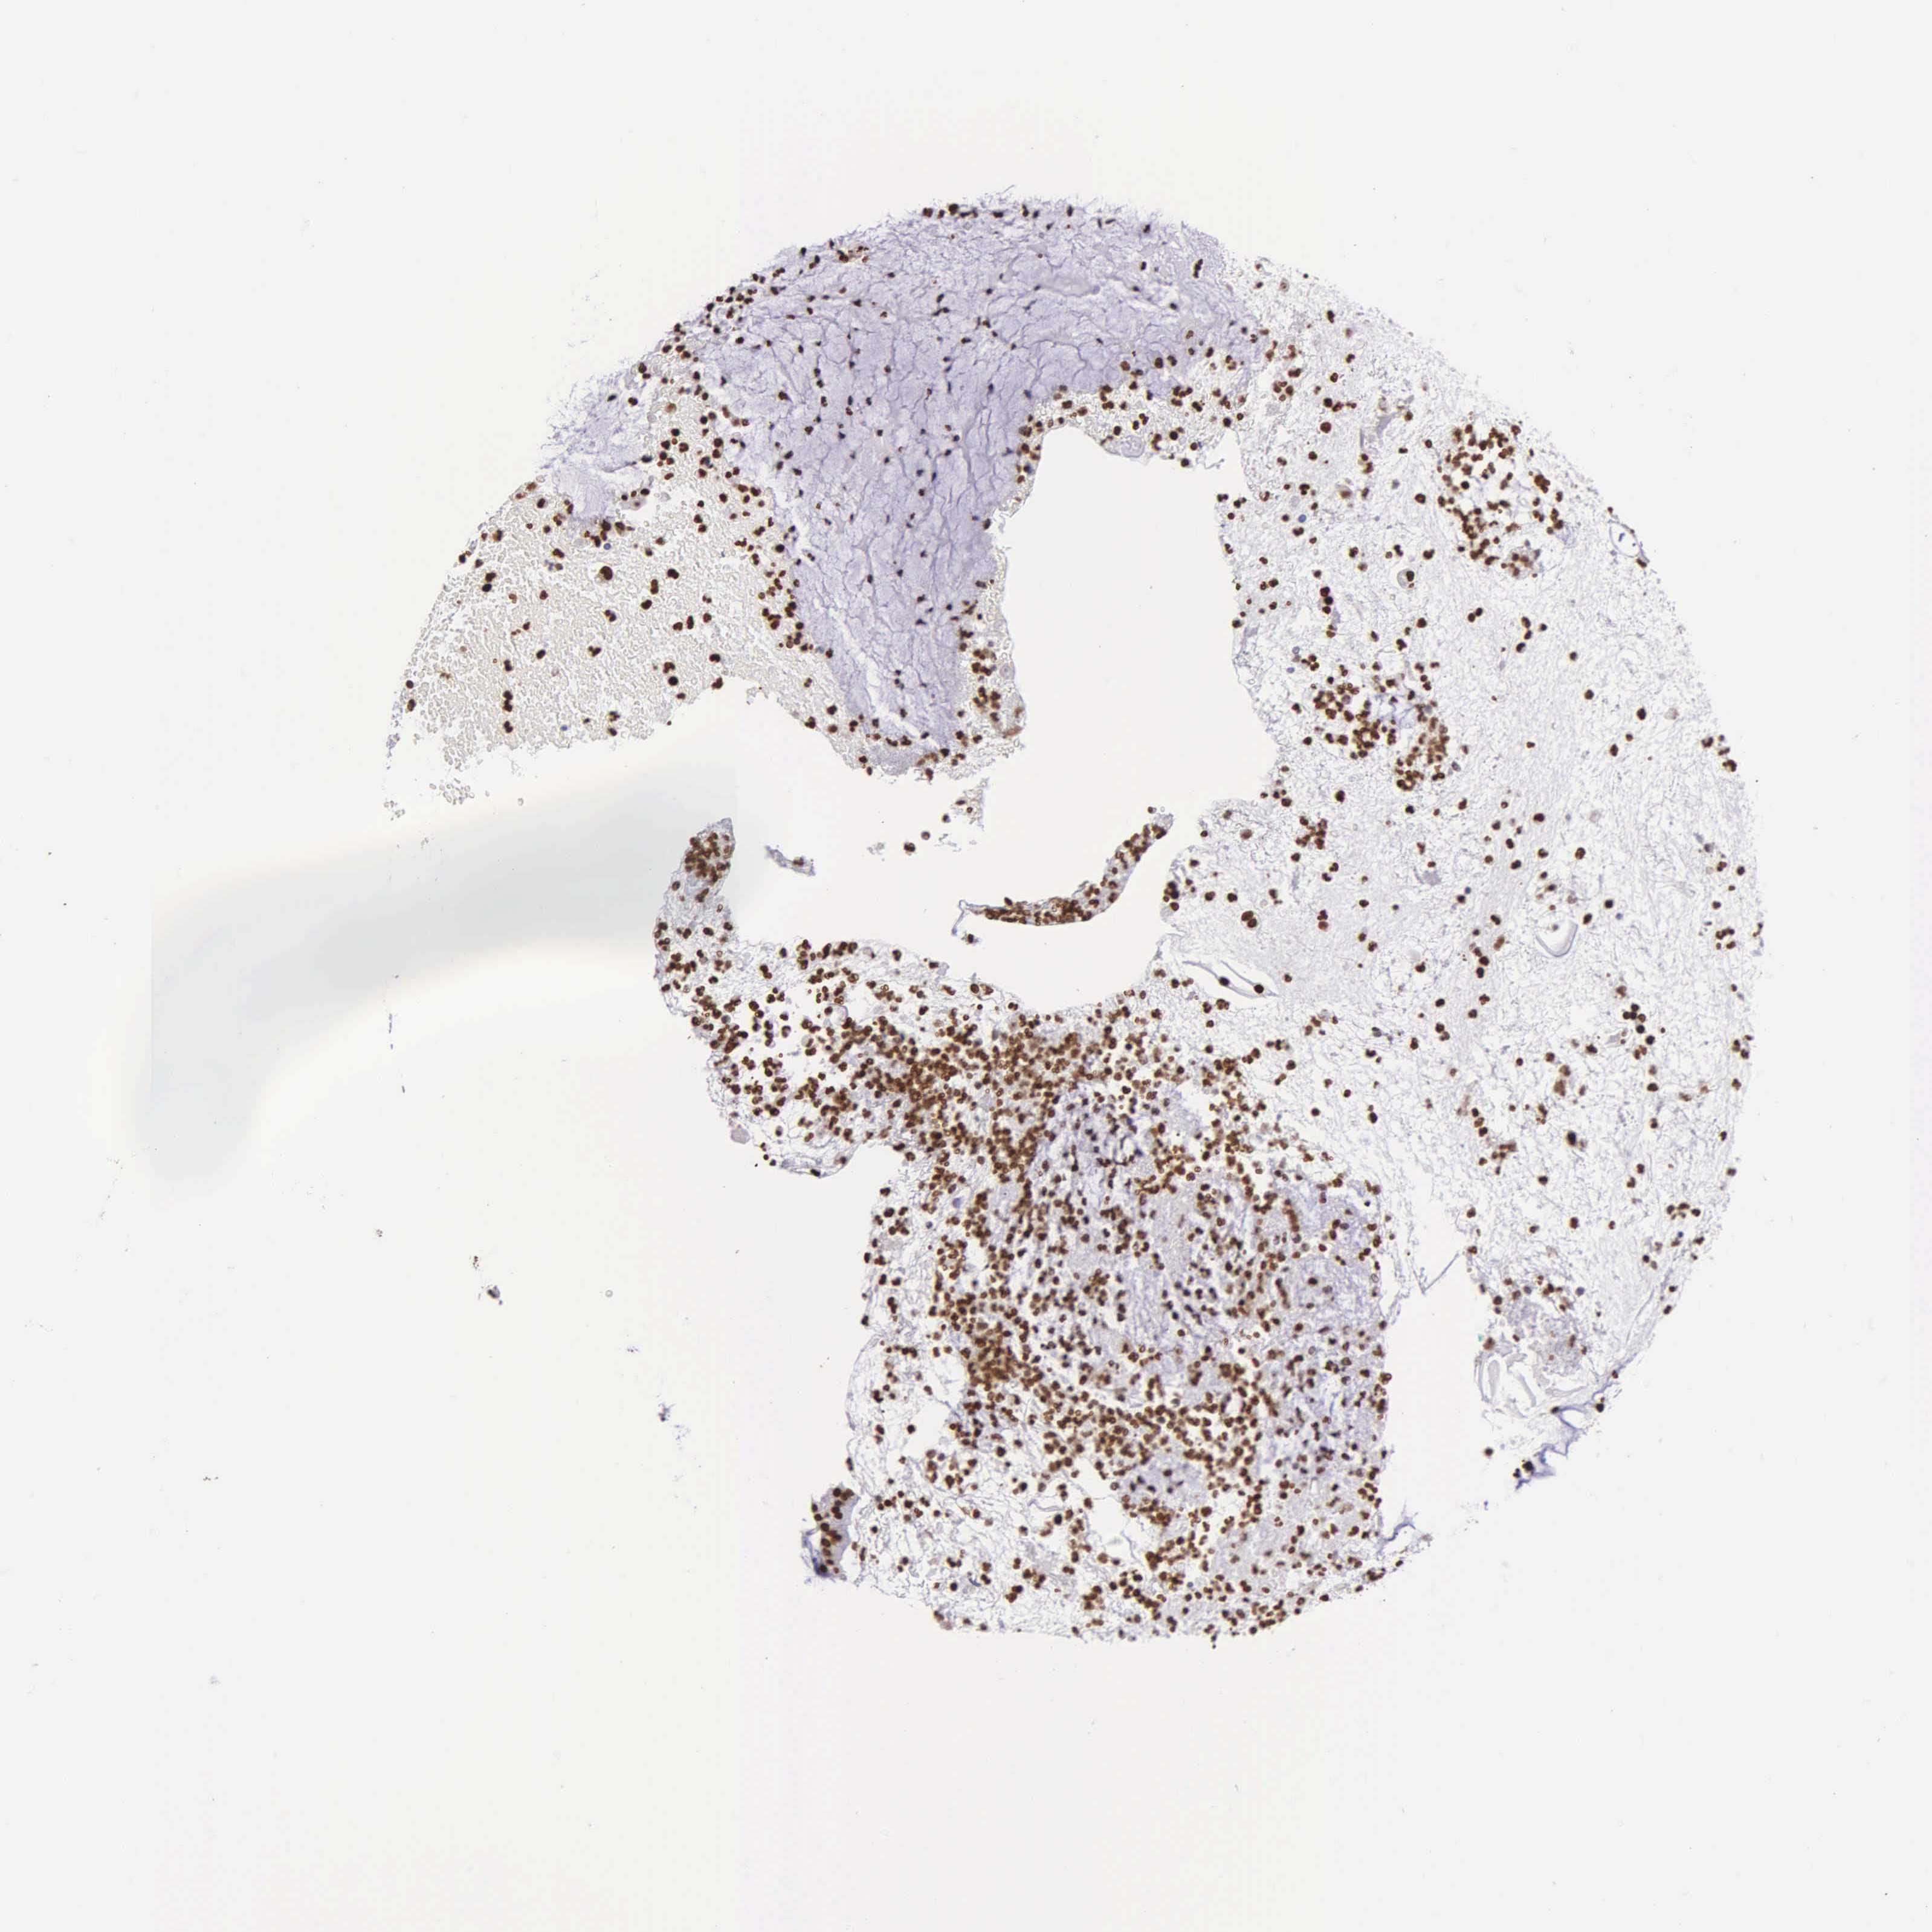

CERVICAL CANCER - Protein expressioni

A mouse-over function shows sample information and annotation data. Click on an image to view it in a full screen mode. Samples can be filtered based on level of antibody staining by selecting one or several of the following categories: high, medium, low and not detected. The assay and annotation is described here.

Note that samples used for immunohistochemistry by the Human Protein Atlas do not correspond to samples in the TCGA dataset.

Antibody stainingi

Antibody staining in the annotated cell types in the current human tissue is reported as not detected, low, medium, or high, based on conventional immunohistochemistry profiling in selected tissues. This score is based on the combination of the staining intensity and fraction of stained cells.

Each image is clickable and will lead to virtual microscopy that enables deeper exploration of all samples and also displays staining intensity scores, fraction scores and subcellular localization as well as patient and tissue information for each sample.

Antibody HPA000843

Staining

High

Medium

Low

Not detected

Intensity

Strong

Moderate

Weak

Negative

Quantity

>75%

75%-25%

<25%

None

Location

Nuclear

Cytoplasmic/membranous

Cytoplasmic/membranous,nuclear

Adenocarcinoma, NOS

Squamous cell carcinoma, NOS